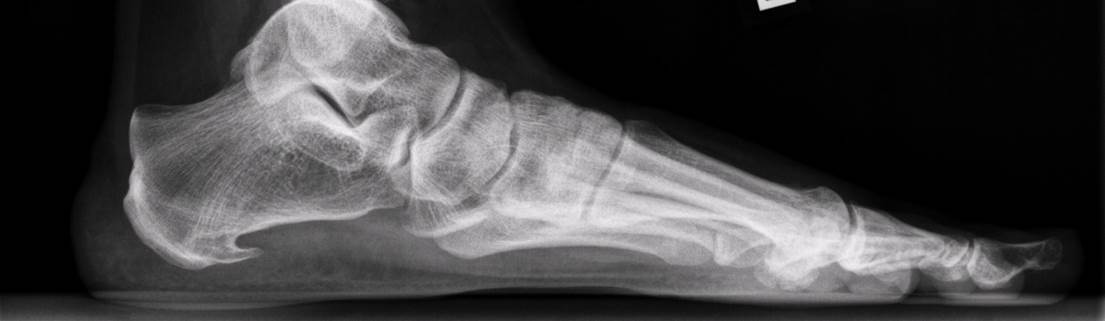

Een hielspoor is een botuitwas (verkalking) aan de onderzijde van het hielbot, het zogenoemde calcaneus. Deze verkalking bevindt zich op de plaats waar de peesplaat onder de voet, de fascia plantaris, aanhecht. Een hielspoor is goed zichtbaar op röntgenfoto’s en kan ook met echografisch onderzoek worden vastgesteld.

Een röntgenfoto kan een hielspoor zichtbaar maken, maar is niet altijd noodzakelijk. Met echografie kan de dikte en kwaliteit van de fascia plantaris worden beoordeeld en kan worden vastgesteld of er sprake is van overbelasting of degeneratie.